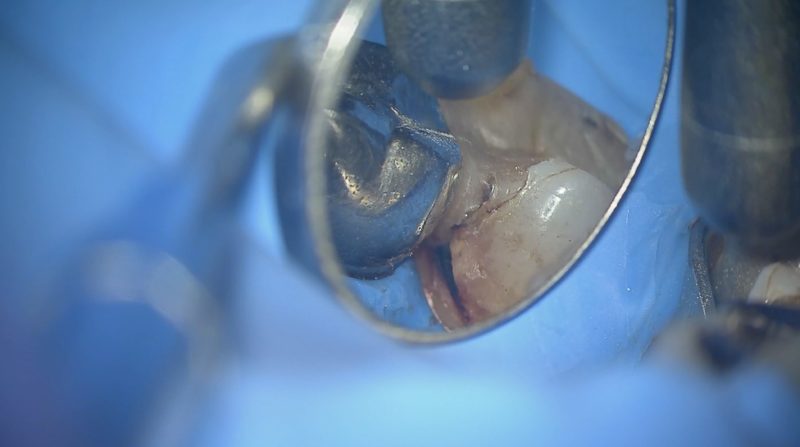

すでに修復物が入っていますが近心・遠心・頬側・近心頬側隅角部に縁下う蝕(深い虫歯)がありました。

近心隅角に虫歯が認められます。

修復物の近心側を削除していくと、大きな虫歯が出てきました。

一番奥の歯のこの部分はたいへん見にくいところですが、ミラーテクニックを修得することで見える範囲が大幅に増え、治療の確実性が上がります。